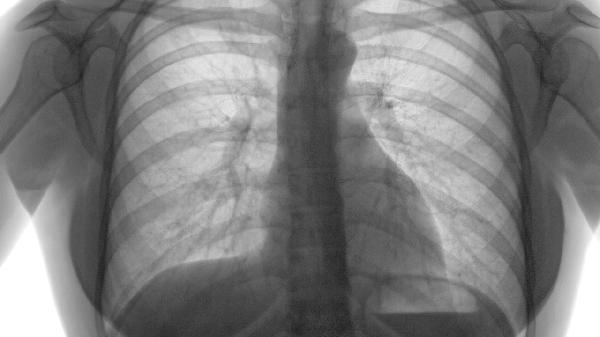

重度肺气肿常见症状及有效治疗药物有哪些

肺气肿的治疗通常会使用支气管扩张剂、糖皮质激素、祛痰药、抗生素以及抗氧化剂等药物来缓解不适。这种疾病的主要诱因包括长期吸...

肺气肿合并肺大泡的治疗方式主要包括戒烟、使用支气管扩张剂、糖皮质激素治疗、肺减容手术以及肺移植。1、戒烟:吸烟是引发肺气...